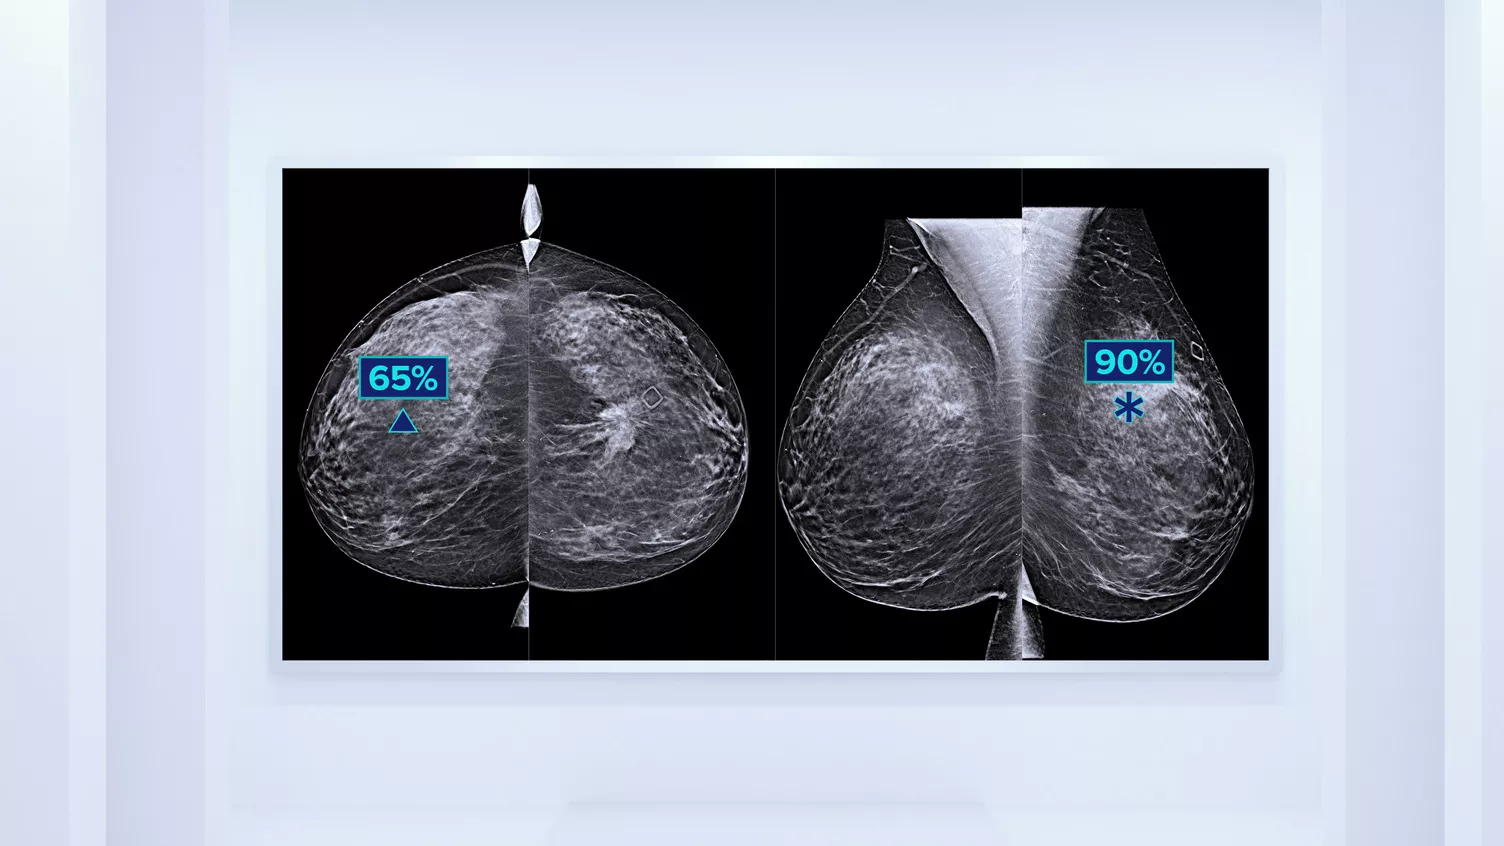

Genius AI™ Detection Technology

Algoritmo di deep-learning progettato per supportare il radiologo nell’individuazione delle aree sospette e nella diagnosi4,9,10, a partire dalle immagini di tomosintesi ottenute dai sistemi mammografici Hologic Dimensions. Individua le lesioni ricercando in ogni sezione della serie di immagini. Le aree sospette vengono evidenziate per la lettura contestuale sulla stazione di lavoro.

È noto che una maggiore densità del tessuto mammario aumenta il rischio di tumore.11,12 È pertanto essenziale disporre di un'analisi accurata e obiettiva. Grazie al machine learning, il software Quantra analizza la struttura e l'aspetto del tessuto mammario nelle immagini 2D e di tomosintesi e classifica le mammelle in quattro categorie di rischio per la composizione.13